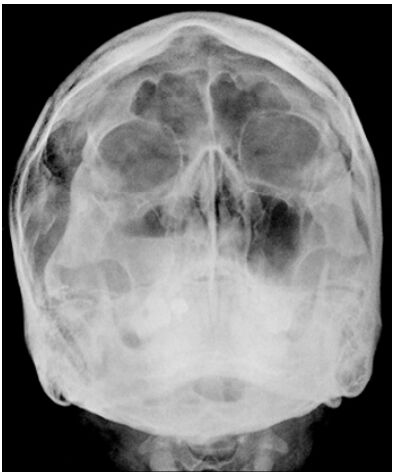

69.附圖中,所標示的牙周炎齒槽突(alveolar process)變化,最可能為何?

(A)頰側或舌側皮質板喪失(buccal or lingual cortical plate loss) (B)根叉侵犯(furcation involvement) (C)齒間陷口(interdental crater) (D)水平骨缺損(horizontal bone loss)